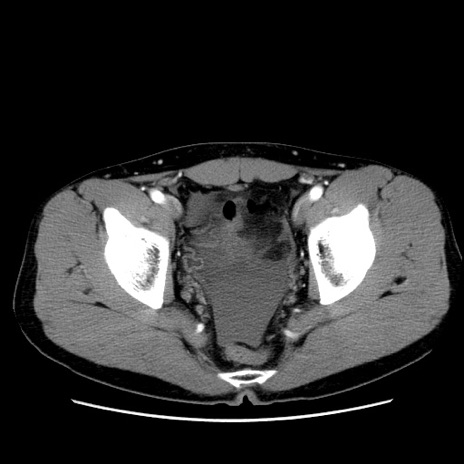

症例36(横断像)

【症例】20歳代 男性

【主訴】心窩部痛

【現病歴】今朝より上腹部痛あり。一旦軽快していたが再度出現したため救急要請。昨日夕に白身の魚を含む刺身を食べた。

【身体所見】BP 136/89mmHg、HR 74/min、BT 37.0℃、腹部:膨満、軟、心窩部に圧痛あり。反跳痛なし、筋性防御なし、腸雑音やや亢進あり。

【データ】WBC 17700、CRP 0.48